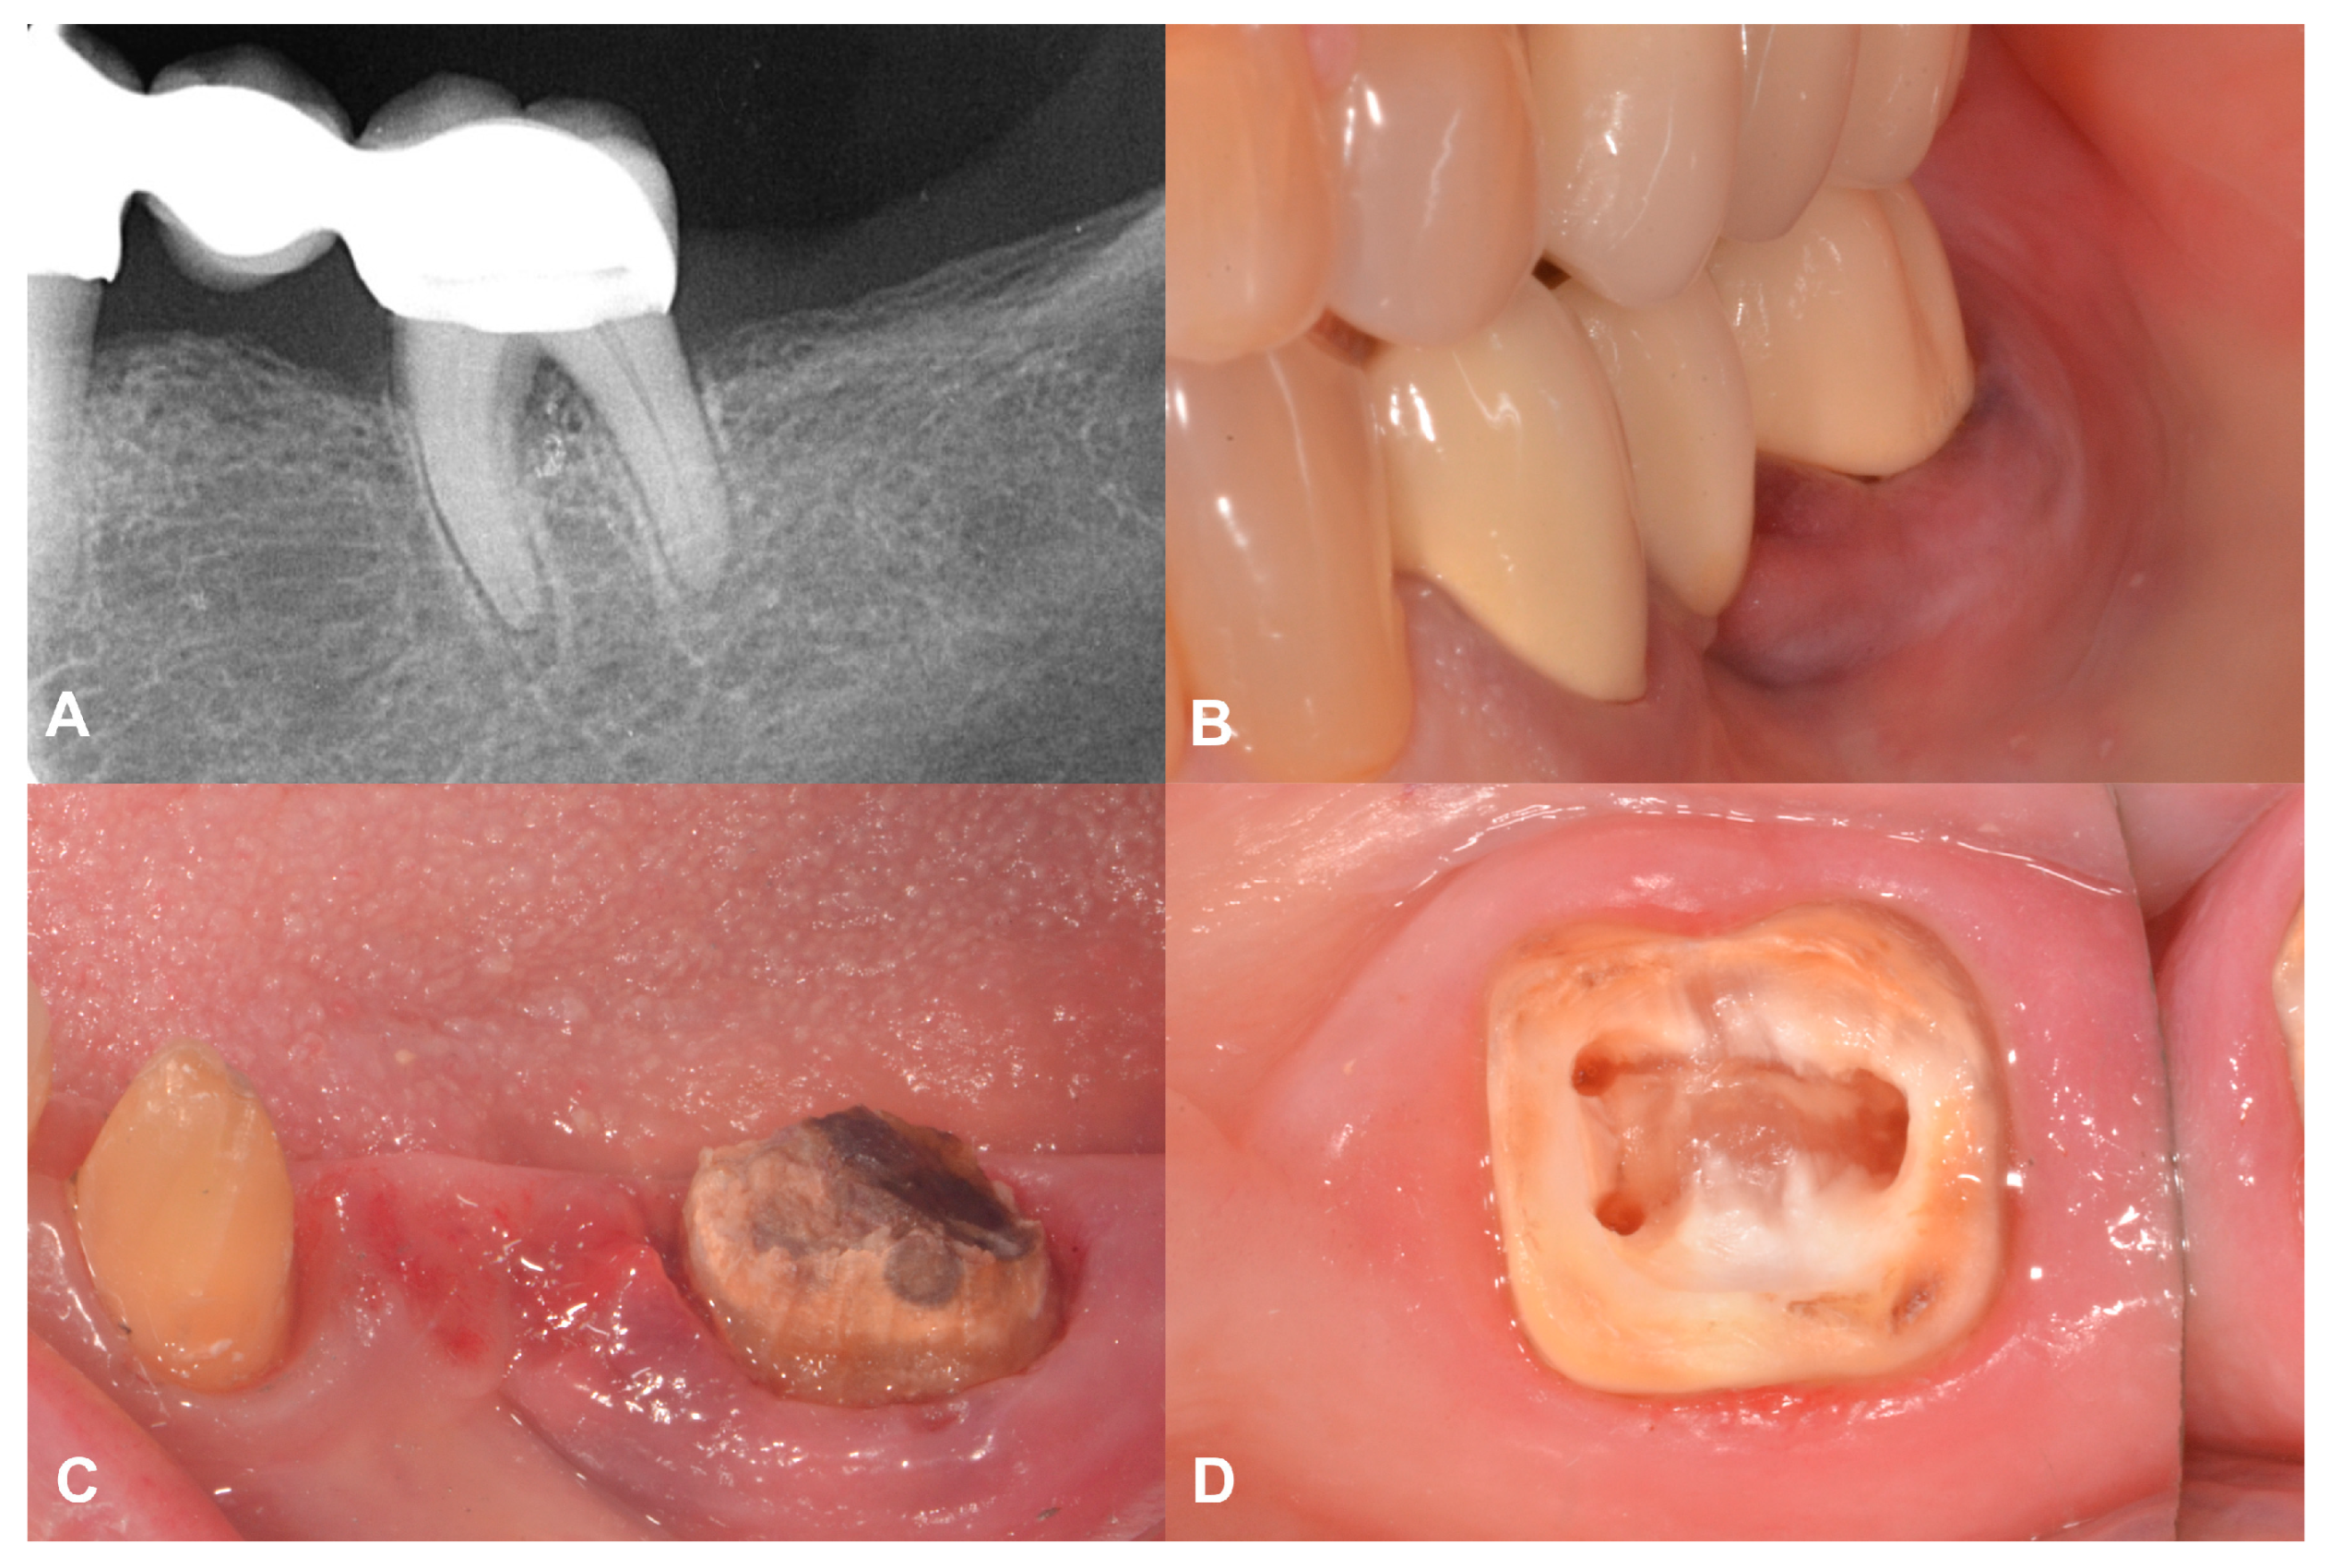

2.2. Case Presentation #1

2.2.1. Anamnesis, Physical Examination

2.2.2. Treatment